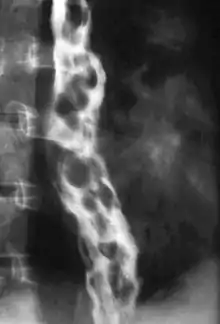

Dilated submucosal veins are the most prominent histologic feature of esophageal varices. The expansion of the submucosa leads to elevation of the mucosa above the surrounding tissue, which is apparent during endoscopy and is a key diagnostic feature. Evidence of recent variceal hemorrhage includes necrosis and ulceration of the mucosa. Evidence of past variceal hemorrhage includes inflammation and venous thrombosis.